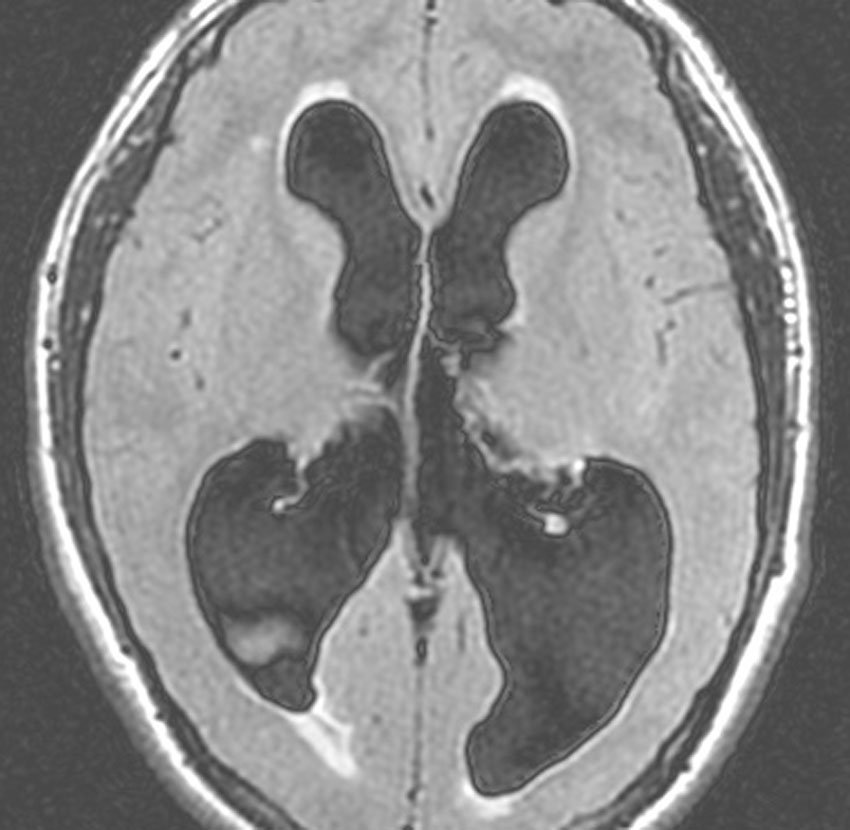

高度の閉塞性水頭症です。このくらいになるといつ意識がなくなっても,呼吸が止まってしまってもおかしくありません。ですから,緊急手術をします。ドレナージ,シャント術,第3脳室開窓術などです。原因となっている脳腫瘍を取り除くことで解決することもあります。

高度の水頭症です。でもこれは幼少期から10年くらい同じような水頭症で経過していると考えられる例です。右側の画像で中脳視蓋グリオーマがみえます。中脳水道狭窄の緩徐な進行によって生じた停止性水頭症 arrested hydrocephalusです。この時点で普通の大学生で無症状です。水頭症に対してはなにも治療をしないで経過を見ます。停止性水頭症にシャント手術は絶対にしてはいけないし,内視鏡による第3脳室開窓術も思わぬ合併症を招くことがあります。